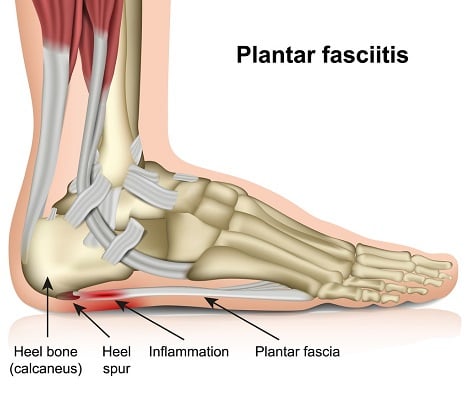

Kenali apa itu Heel Spur dan cara cara merawatnya discount, Dr Zubaidi Hj Ahmad SAKIT TUMIT HEEL SPUR Heel Spur atau calcaneal spur ialah keadaan yang disebabkan oleh pemendakan kalsium tidak normal sehingga mengakibatkan berlakunya benjolan tulang di bahagian... discount, Armels Academy APA ITU HEEL SPUR Heel Spur adalah. Facebook discount, Heel Spur Punca Simptom dan Rawatan The Diagnosa discount, 104KB 2001 null null null null null null null 1 2003 null gdUFSGid890e3M discount, Heel spur discount, Two Places Where Heel Spurs Can Form Blog discount, Heel Spurs Treatment Podiatrist Foot Doctor Punta Gorda FL 33950 and Port Charlotte FL 33952 discount, Heel Spur Causes Management Singapore Straits Podiatry discount, Foot Pain Treatment Without Injections Or Surgery discount, Plantar Fasciitis Heel Pain Stratagies to relieve pain discount, Causes and Risks of Heel Spurs Blog discount, The Definition of a Heel Spur discount, Heel Spurs Causes Symptoms and Treatment discount, Homeopathic Treatment For Heel Spur discount, Treating Bone Spurs discount, What Is a Bruised Heel discount, Bone Spurs Foot and Ankle Clinic DRHC Dubai discount, Plantar calcaneal spurs in older people longitudinal traction or vertical compression Journal of Foot and Ankle Research Full Text discount, Calcaneal Spurs Physiopedia discount, Heel Spur Taping discount, What Is a Heel Spur discount, AR Fisioterapi Apakah itu BONE SPUR Bone. Facebook discount, Painful Heel Spur Management in Singapore Podiatry Clinic discount, Plantarfasciitis What the Heel discount, Penyelesaian Heel Spur 5 Cara Iswanah Fisioterapi Atasi Iswanah Physiotheraphy discount, Heel Spur Treatment Relief The Foot Practice Singapore discount, Heel Pain Spur Pain aka Plantar Fasciitis My Bowen Therapy discount, What is Heel Spur and how to correct it relieve your pain discount, Calcaneal Spurs Physiopedia discount, Heel Pain Causes Best Treatment Options In Malaysia discount, Tumit Spur Punca Pengurusan Singapura Straits Podiatry discount, Plantar Fasciitis Home Consultant Orthopaedic Surgeon discount, Heel Spur or Calcaneal Spur discount, Iswanah Shah Alam APA ITU HEEL SPURS Plantar fasciitis Plantar fasciitis adalah keadaan di mana tisu plantar fascia yang menghubungkan tulang tumit. Instagram discount.